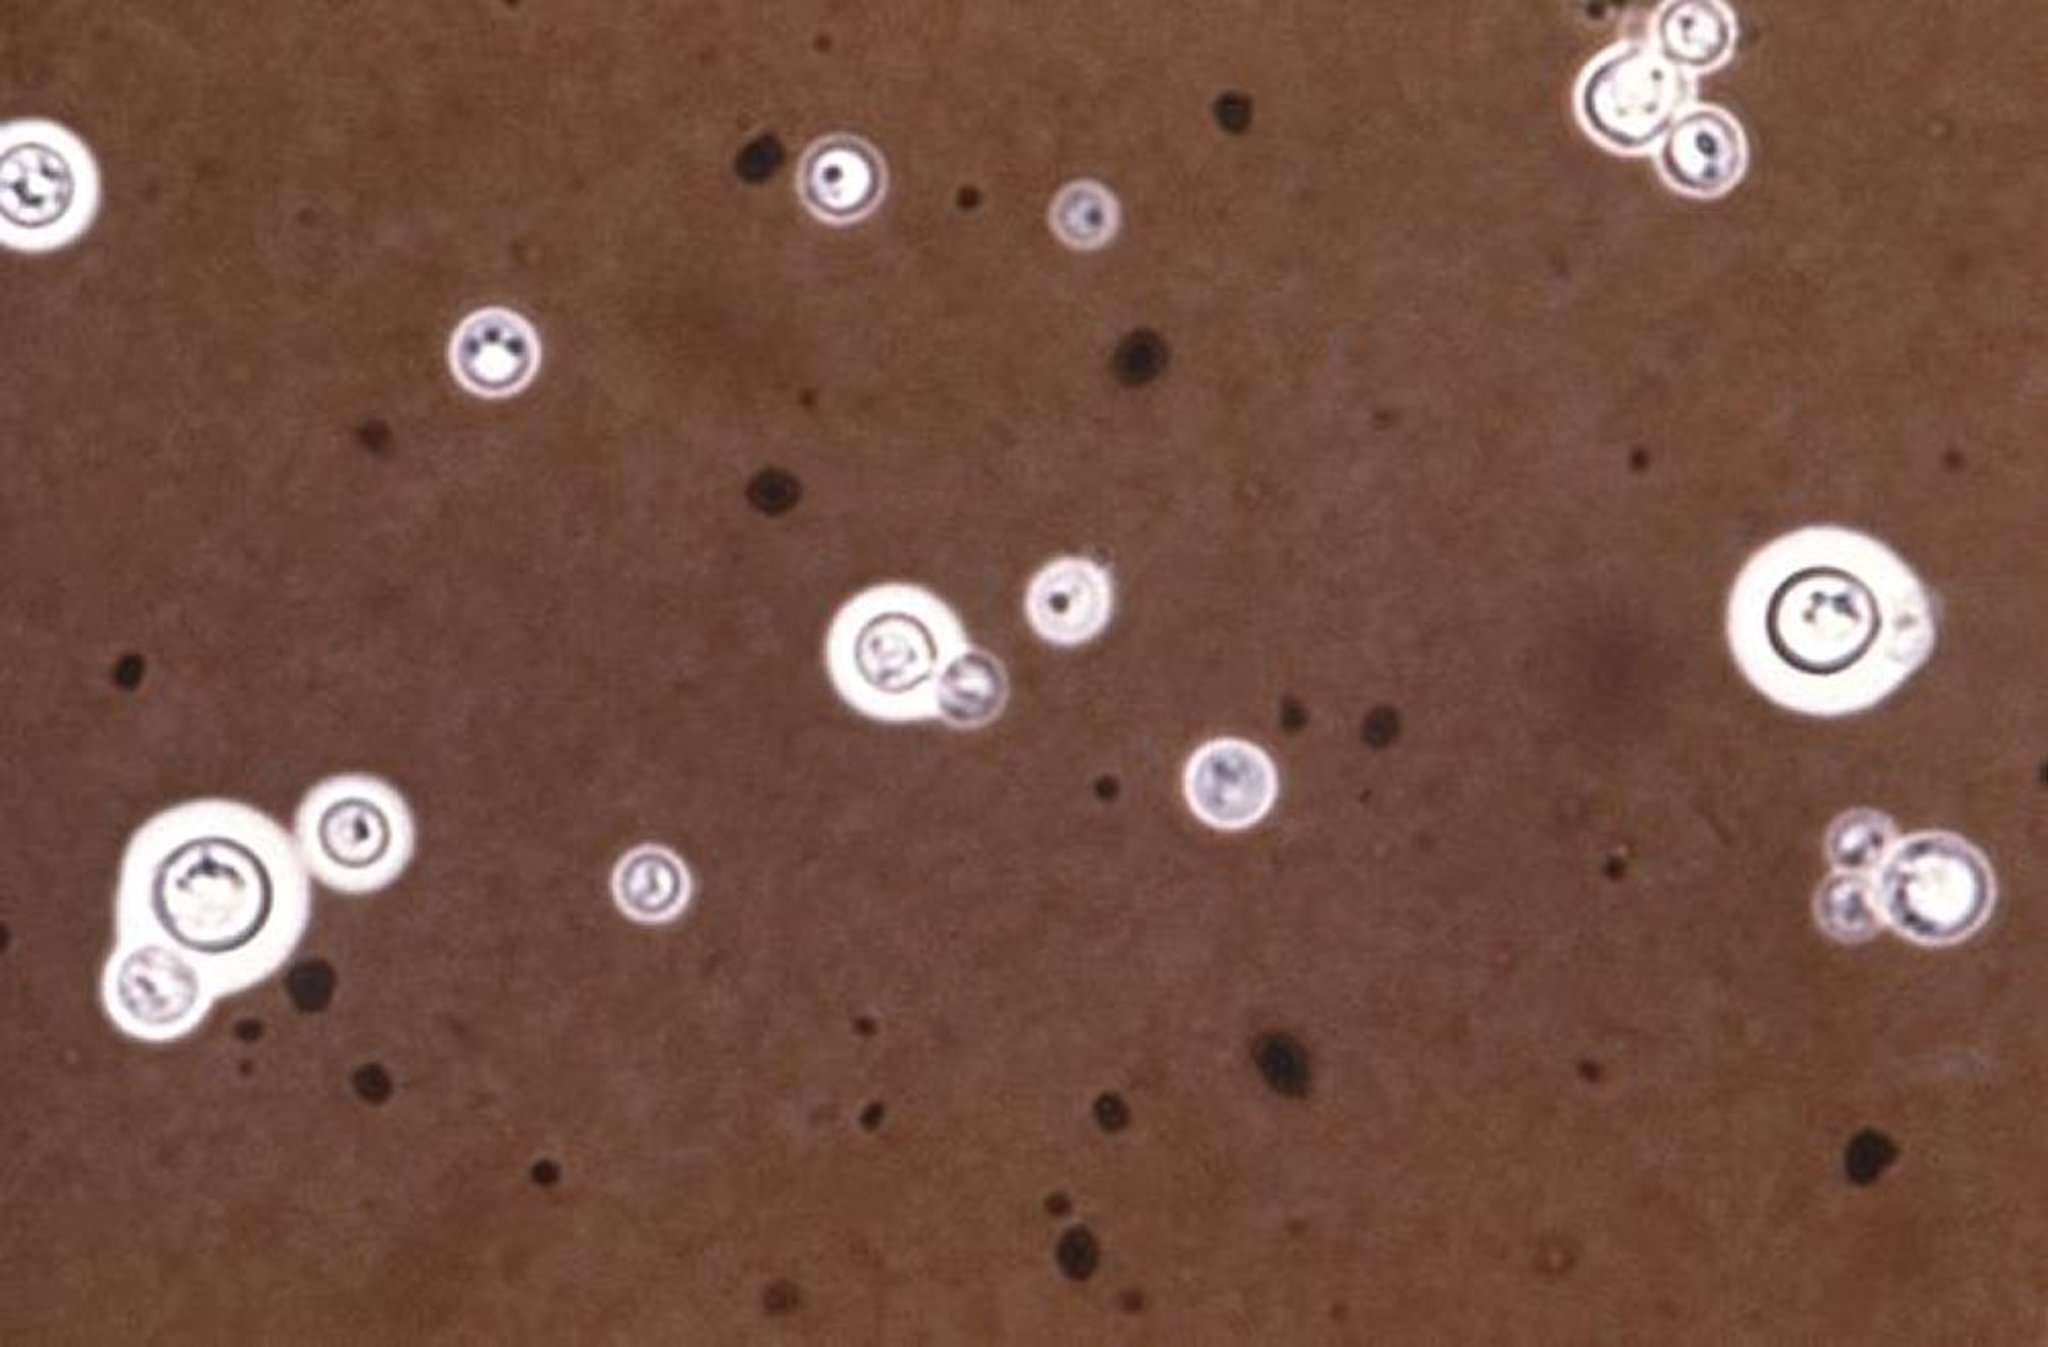

Tinta china (Cryptococcus neoformans)

Esta imagen es una microfotografía optica de C. neoformans coloreado con tinta china. La tinción con tinta china hace que las cápsulas alrededor de los microorganismos sean visibles como un halo (anillo luminoso).

CDC/Brinkman/SCIENCE PHOTO LIBRARY